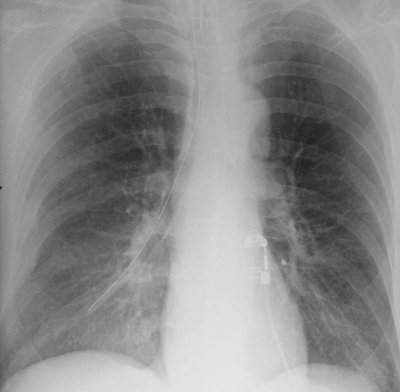

none should be present during diastole. If the catheter is short, dislodgment may occur, and the catheter may enter the right atrium, pulmonary artery, SVC, or coronary sinus. If the lead is too long, a bend in the wire may occur, causing lead fracture (Fig. 5-22). A redundant lead may also perforate the myocardium; this complication generally occurs at the time of or within a few days after insertion. The frontal or lateral radiograph will show the catheter tip outside or within 3 mm of the edge of the cardiac silhouette (Fig. 5-23). Perforation can lead to cardiac tamponade or postcardiotomy syndrome. Inflammation and infection can occur within the vein or the generator pocket; the latter occurs in up to 5% of patients (20). Major vein thrombosis and pulmonary embolism are additional complications of pacemaker insertion.

FIGURE 5-22. Looped pacer lead. PA (A) and lateral (B) chest radiographs show looping of the pacer lead over the area of the expected tricuspid valve (arrow). This positioning can result in dysrhythmia, lead fracture, or myocardial perforation.

FIGURE 5-23. Displacement of pacer lead. A: PA chest radiograph shows that the tip of the pacer lead (arrow) is beyond the expected right ventricular wall. B: CT shows the lead outside of the myocardium (arrow). A more inferior image (not shown) showed that the lead tip was within the anterior chest wall.